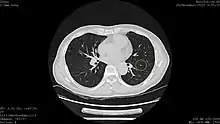

| Lung cancer screening | |

![]() Computed tomography (CT) scanner, the usually recommended screening technique | |

| Purpose | identify early lung cancers before they cause symptoms |